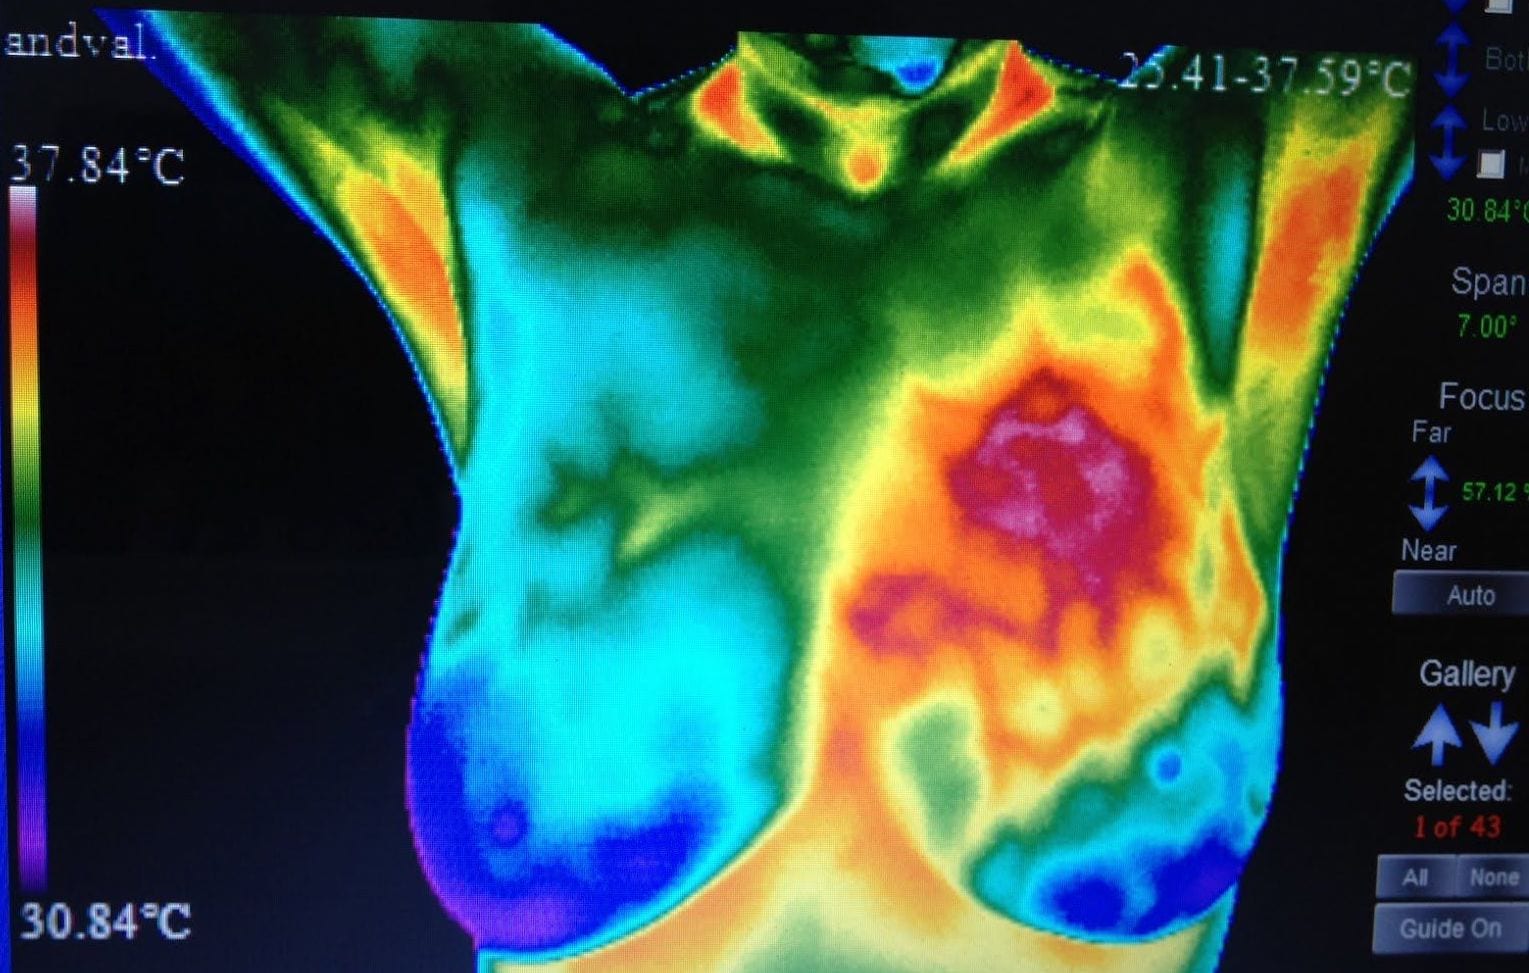

Toms River X-Ray, CT & MRI Center has been deemed a Center of Excellence by the American College of Radiology for our expertise in: Breast Imaging, Breast Ultrasound, CT Scan, CT Lung Screening, Mammography, MRI, Nuclear Medicine, PET/CT, Stereotactic Breast Biopsy, and Ultrasound.